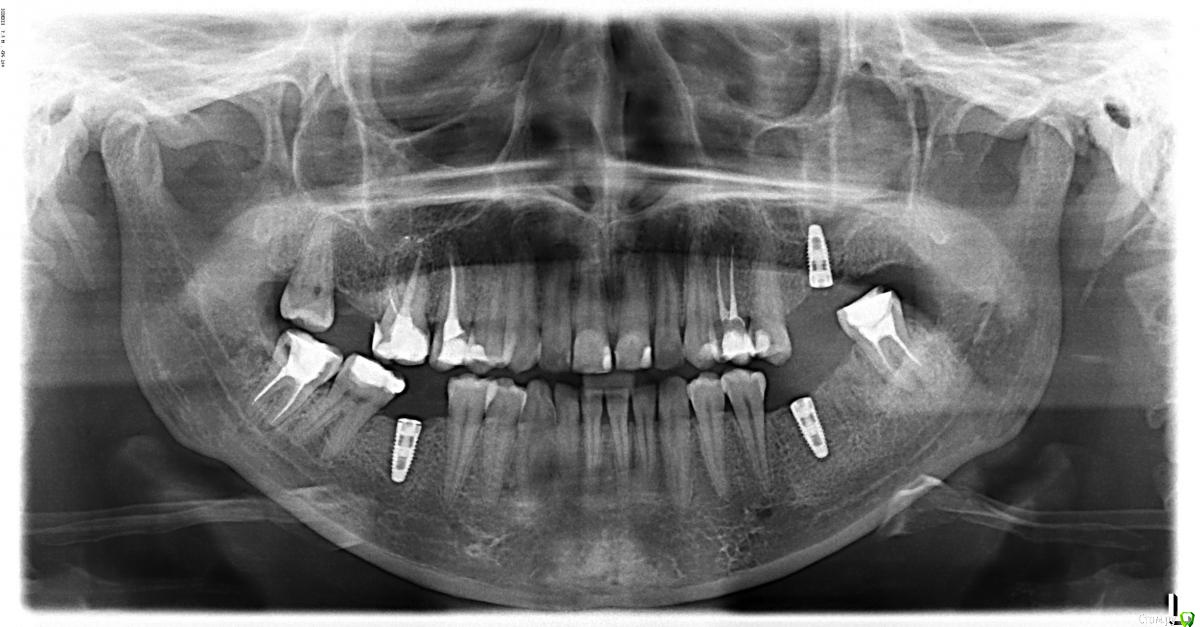

Madira Опубликовано 17 июля, 2016 Автор Поделиться Опубликовано 17 июля, 2016 Здравствуйте, уважаемые врачи. Новую тему заводить не имею смысла,продолжаю эту. Сделали мне реимплантацию, выкладываю снимок. Сейчас получше все выглядит? Есть шансы на успех? Спасибо! Ссылка на комментарий

red_butler Опубликовано 18 июля, 2016 Поделиться Опубликовано 18 июля, 2016 Пока нормально, справа заглушка не докручена. 1 Ссылка на комментарий

red_butler Опубликовано 18 июля, 2016 Поделиться Опубликовано 18 июля, 2016 Кстати, почему опять эту систему имплантов использовали? Ссылка на комментарий